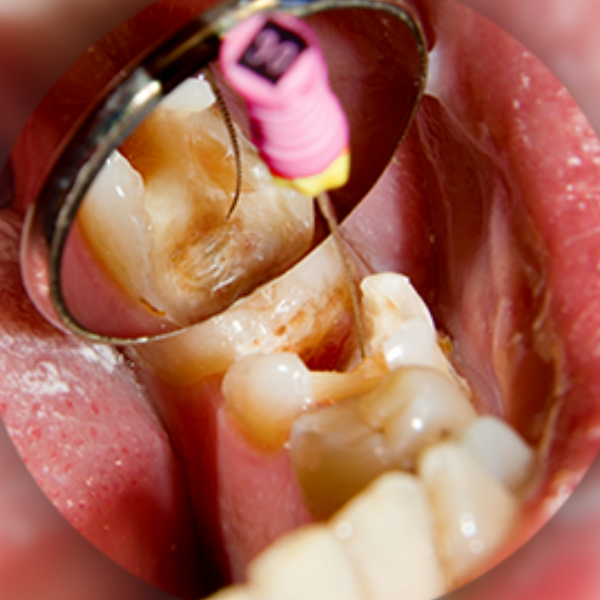

Root canal treatment is a dental procedure that removes infected or damaged pulp inside a tooth. After cleaning and disinfecting the root canal, the tooth is sealed and restored with a filling or crown to prevent further infection.

At our advanced RCT Clinic in Hyderabad, we use rotary instruments and magnification tools to improve precision and patient comfort.

The infected pulp tissue is carefully removed under local anesthesia.

Cleaning and Shaping

The root canals are disinfected and shaped for sealing.